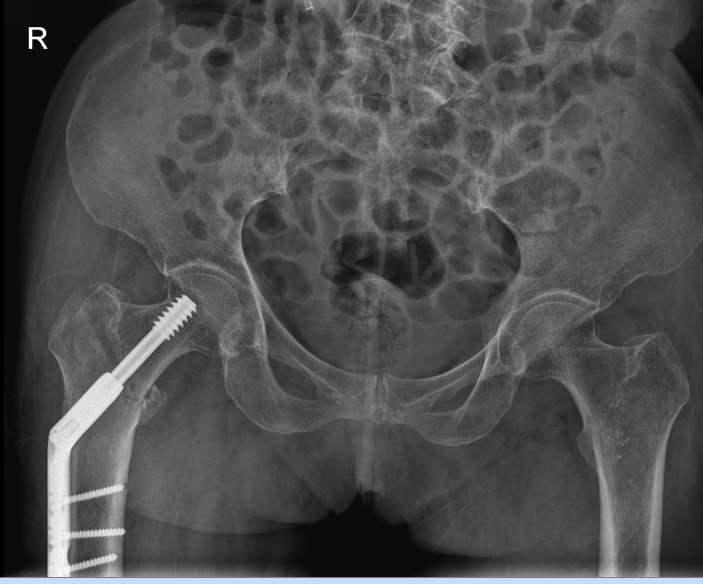

吳志斌主任通過CT+三維重建先行拟定詳細手術方案,提前做了精心準備。根據患者的年齡特征,爲其選擇最佳的半髋置換方案,并采用雙動人工股骨頭,提高活動範圍,減少髋臼磨損。

△右側(R)是賴婆婆3年前跌斷股骨術後,左側是本次手術術後。